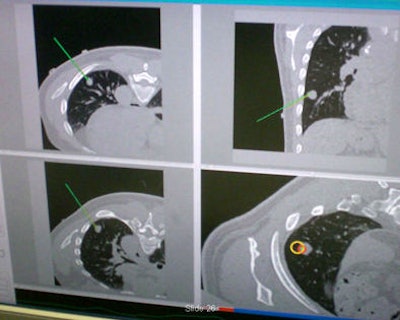

"It's line-of-sight, it's very accurate, but you can't track inside the body," he said. "What electromagnetic tracking allowed us to do was track inside the body, and now we have the chance to use image-guided systems for abdominal intervention -- and it opens up a whole new field for this kind of surgery. We can build a system where we now have a field generator, a sensor coil with needle, track the needle, and give an image overlay on a four-quadrant display in all these systems" (Aurora electromagnetic tracking, Northern Digital) Cleary said. The graphic user interface shows the planned path is in green and the virtual overlay in yellow.

Instead of looking back and forth and checking with the scanner as you advance the needle, you can watch the virtual reality display and put your needle down, he noted. When the image seems right, the interventionalist goes back for a confirming x-ray image; the procedure can then be performed with conebeam CT -- which in a sense has brought CT to the interventional suite.